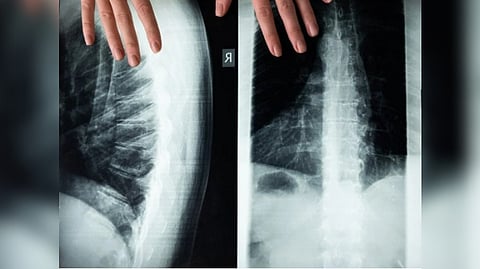

BIRMINGHAM: According to the University of Birmingham, scientists discovered that blocking the inflammatory response in the spinal cord may reduce damage after spinal cord injury.

Researchers led by Professor Zubair Ahmed, Professor of Neuroscience and lead for the Neuroscience and Ophthalmology Section at The University's Institute of Inflammation and Ageing, used animal models to demonstrate that AZD1236 can promote significant nerve regeneration, with a dramatic 80 per cent preservation in nerve function following spinal cord compression injury.

Crucially, this translated into an 85 per cent improvement in movement and sensation.